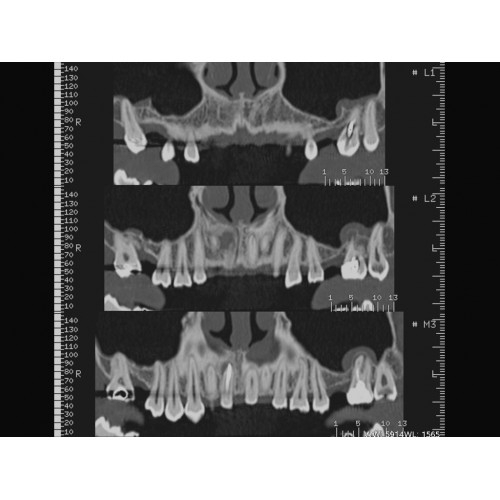

• Широкая область применения: от неврологии до кардиологии и онкологии.

КТ аппарат GE Optima CT520 используется для диагностики широкого спектра заболеваний:

Неврологические исследования

• Выявление инсультов, опухолей головного мозга и травматических повреждений.

• Диагностика заболеваний позвоночника и межпозвоночных грыж.